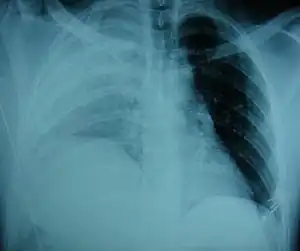

An X-ray showing a raised diaphragm on the right[1]

Physical examinations are not accurate, as there is usually no specific physical sign that can be used to diagnose this condition.[3] Thoracoscopic and laparoscopic methods can be accurate.[12] Chest X-ray is known to be unreliable in diagnosing diaphragmatic rupture;[4] it has low sensitivity and specificity for the injury.[5] Often another injury such as pulmonary contusion masks the injury on the X-ray film.[6] Half the time, initial X-rays are normal; in most of those that are not, hemothorax or pneumothorax is present.[4] A nasogastric tube from the stomach may appear on the film in the chest cavity; this sign is pathognomonic for diaphragmatic rupture, but it is rare.[4] The X-ray is better able to detect the injury when taken from the back with the person upright, but this is not usually possible because the person is usually not stable enough; thus it is usually taken from the front with the person lying supine.[5] Positive pressure ventilation helps keep the abdominal organs from herniating into the chest cavity, but this also can prevent the injury from being discovered on an X-ray.[4]